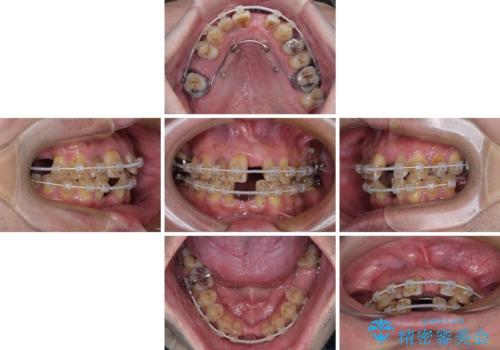

矯正治療を行いながら、欠損部はインプラントによる補綴治療を希望されたため、補助装置を用いたワイヤー矯正によりスペースを確保しながら歯列を整え、適宜インプラントを埋入していくこととしました。